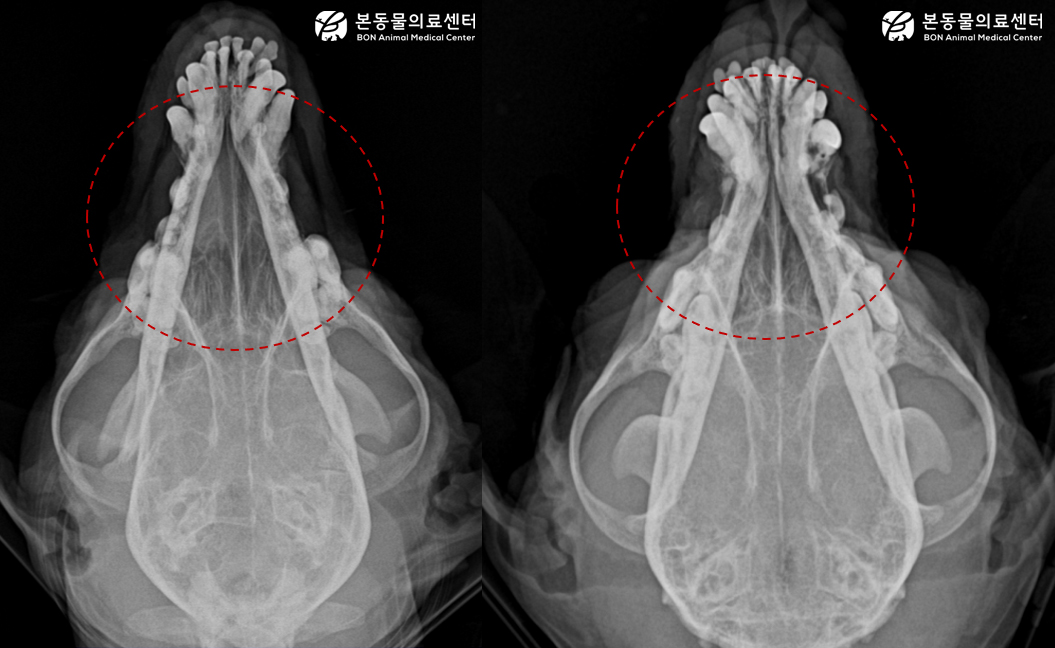

방사선 상 Rhintis로 인한 유축 비강 전방부 밀도가 증가해 있었고, 농성 비루를 직접 도말해 현미경으로 확인한 결과 다수의 간균이 확인되었다.

환자와 같이 콧물로 내원하게 되면, 우선 기본 두개골 방사선 촬영을 실시한다.

그 결과 우측 비강의 연부조직 밀도 상승이 확인되어, 우측 비염 및 연령 등을 고려 시 비강 종양 등의 가능성이 고려되었고, 정확한 평가를 위해 CT 검사가 추천되었다. 상위 검사를 실시하기 전 비루 도말 상 다수의 간균이 확인되어 우선 보호자 분과 상담하여 호흡기계 감염 질환 여부를 확인해 보기로 하였다.

항 진균제 치료 2주 후 재촬영한 방사선 사진 결과, 우측 비강 전반부의 밀도 상승은 개선되었으며, 임상 증상 또한 소실되었다.